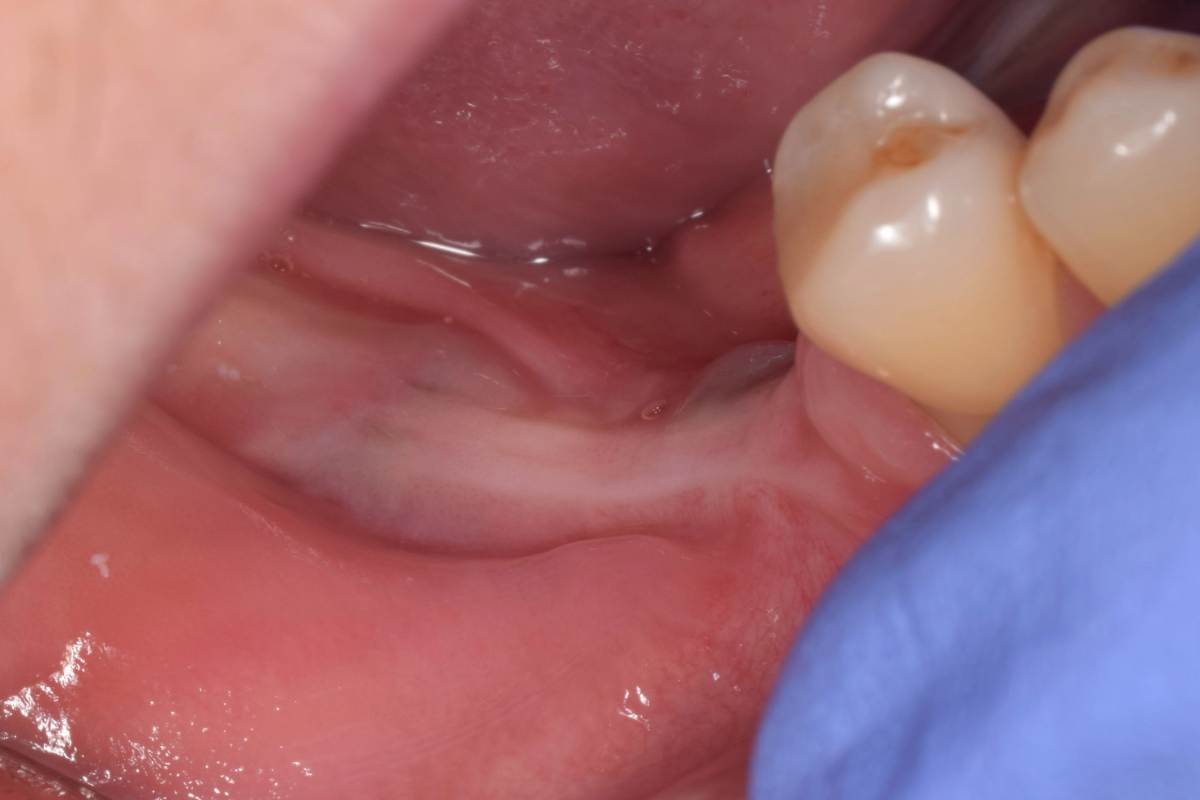

Да, фото есть. Но вспоминаю клин случай, там на первом этапе уже были проблемы.

СдТ по Едранову, видимо получил воспалительный процесс. В результате СДТ усело более чем на 50%.  Потом через 1.5 мес. открытие имплантов и ССТ. Некроз у одного импланта.Думаю связано с неполным ушиванием и ССТ с эпителием. Восстановление слизистой после некроза 2 мес и временное протезирование. Сейчас все выглядит достойно, но лишние нервы.

Нашел фото результата на времянках. Оно конечно не очень информативное,  был один и поэтому так получилось сфоткать

IMG_20250430_214632.jpg